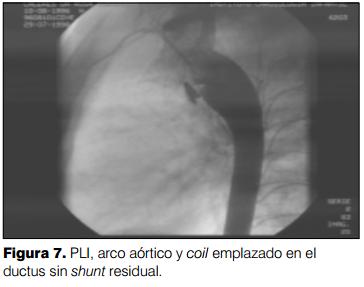

Para proceder al emplazamiento del dispositivo se utilizó electivamente la vía transarterial para la colocación de coils (97%) (figuras 6 a 10), y la vía transvenosa sólo en pocos casos. Los coils se pueden implantar sea por vía venosa o por vía arterial, según la experiencia del equipo actuante. En nuestra serie se implantaron entre dos, tres, cuatro o cinco coils por paciente en forma simultánea o sucesiva en 47 pacientes, y en 89 pacientes se utilizó un solo coil. Los dispositivos de Grifka o Amplatzer se implantan por vía transvenosa (figuras 11 a 18). Los coils son dispositivos espiralados con un núcleo central metálico rodeado de un material trombogénico que una vez liberado adopta una forma preestablecida. De esta manera, el cierre del defecto depende de la colocación del dispositivo y de la acción del organismo creando un trombo dentro del mismo y posterior epitelización formando parte de la pared aórtica. Dichos dispositivos vienen en estuches cilíndricos del tamaño de los catéteres y se los enumera con tres dígitos, el primero indica el grosor del mismo (35-38-52) el segundo indica el diámetro de la vuelta de espira una vez liberado expresado en milímetros (3-4-5-8-10-12) y el último indica la longitud del dispositivo en centímetros (2-3-5-8-10). La bolsa de Grifka consiste en un receptáculo que admite el enrolle en su interior de un coil de gran longitud. El dispositivo de Amplatzer es cilíndrico, de un material denominado nitinol con material trombogénico en su interior. Cada dispositivo viene caracterizado por tres dígitos: uno correspondiente al diámetro menor, otro correspondiente al diámetro mayor y el tercero correspondiente a la longitud del mismo.

Una vez implantado el dispositivo se comprobó la correcta posición del mismo desde el punto de vista angiográfico y se corroboró la existencia o ausencia de shunt residual. El paciente queda internado 12 horas con controles vitales, pulso y presión arterial del miembro en donde se realizó la punción arterial. Es dado de alta con control en policlínica cardiológica en tres meses, desde el punto de vista clínico y ecocardiográfico.